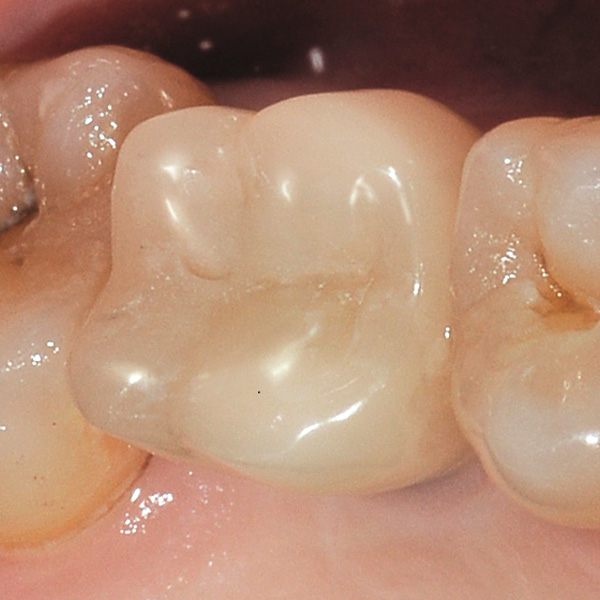

Restaurationen auf Implantaten sind besonders hohen Belastungen ausgesetzt. Da dem Patienten der elastische Faserapparat des natürlichen Zahnbetts fehlt, werden Kaukräfte nicht absorbiert, sondern direkt auf die Restauration, das Implantat, den Knochen sowie die Gegenbezahnung übertragen. Die Hybridkeramik VITA ENAMIC verfügt über eine duale Netzwerkstruktur aus Keramik und Polymer. Daraus resultieren eine dentinähnliche Elastizität und die Fähigkeit, Kaukräfte zu absorbieren. Der mehrfarbige Rohling VITA ENAMIC multiColor in der Geometrie EMC-16 ermöglicht aufgrund seiner hohen vertikalen Dimension auch bei atrophiertem Knochen die Herstellung einteiliger, monolithischer Abutmentkronen. Zahnarzt Professor Dr. Alexander Hassel zeigt im folgenden Beitrag, wie er eine Patientin mit dieser Restaurationsform versorgt.